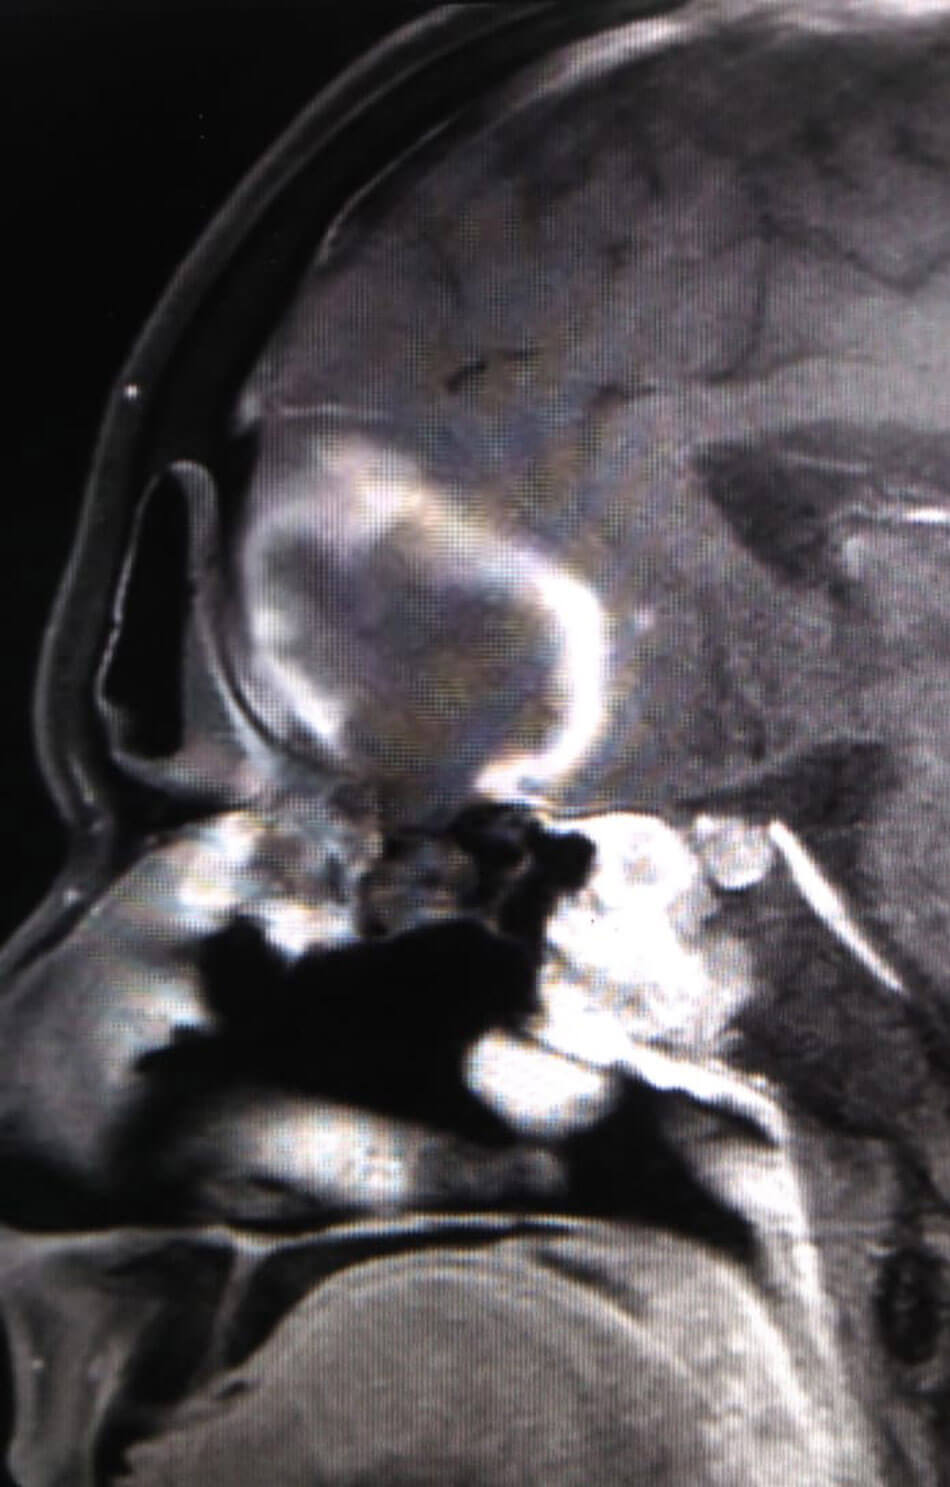

MRI scans of a patient with ROCM showing a large frontal lobe brain abscess

with necrosis of the cribriform plate (coronal and sagittal views).

The initial phase saw late presentations including cerebral mucormycosis. But overall, cerebral involvement is about 5-8%. Also, 2-3% of other patients progress to intracranial involvement in spite of aggressive treatment. Cerebritis is managed conservatively with significantly higher doses of amphotericin B. Focal abscesses have been drained by neurosurgeons. About 20% of patients have had some degree of orbital involvement. Surgical management may range from orbital decompression to selective periorbital endoscopic debridement to orbital exenteration (guided by clinical and radiological findings). Most decisions are tailored to the context.